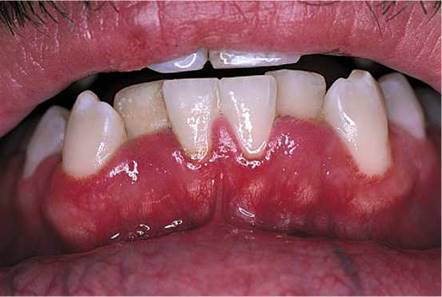

Acute necrotizing gingivostomatitis (also known as ulcerative gingivostomatitis or Vincent's gingivitis), is a severe, noncommunicable disease of young adults resulting from infection by Fusobacterium nucleatum or Borrelia vincentii. Most cases occur suddenly in the spring or autumn. The patients, commonly men with poor oral hygiene, present with gingival bleeding, alteration of taste, gingival pain, malaise, fever, and halitosis. As the disease progresses, a whitish pseudomembrane develops along the gingival margins, with ulceration and blunting of the interdental papillae. Acute necrotizing gingivitis, pictured in Figure 12-57, may be an early feature of HIV infection.

Figure 12-57 Acute necrotizing gingivostomatitis.